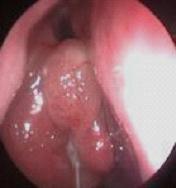

经常鼻塞、流脓鼻涕、头痛多为鼻窦炎、鼻息肉等。